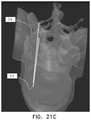

FIG. 21C shows an example of the representations of a portion of an actual tool and the planned insertion path displayed together within a semi-transparent 3D model of a spinal segment, in accordance with some applications of the present invention;

FIG. 22A shows an AP x-ray of two tools being inserted into a vertebra through, respectively, 10-11 o'clock and 1-2 o'clock insertion windows, the AP x-ray being generated using prior art techniques;